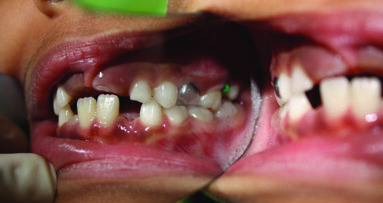

An eight and half year-old girl (LT) attended the paediatric dentistry department of Hamdan Bin Mohammed College of Dental Medicine (HBMCDM) in Dubai Healthcare City for an opinion. The patient’s mother was concerned about the delayed eruption of an upper front tooth (21) that was affecting her child’s appearance (Figs. 1 a, b & c). LT was medically fit and healthy with no history of previous dental trauma. She was in the mixed dentition stage. Tooth 11 had erupted 4 months ago in cross bite but 21 had not erupted yet. Its eruption was much delayed (usually erupts at 7 ½ years of age). Looking back at previous x-rays, a DPT was taken a year ago and it was noticed that an important feature was missed. Retrospectively, the presence of a supernumerary tooth ($) in the area of 21 and congenital missing 47 was confirmed (Fig. 2). Two new x-rays, namely upper intra oral periapicals and the parallax technique (distal shift) showed a supernumerary tooth (conical and inverted) in a palatal position (Figs. 3 a & b). LT also had dental caries of her primary teeth (Figs. 4 a & b), had a pronounced gag reflex and was dentally anxious.

Figs. 1 (a, b & c). An 8 ½ year old girl presented with delayed eruption of 21 and a palpable palatal swelling. Lower teeth were carious; see bitewings in Figure 4